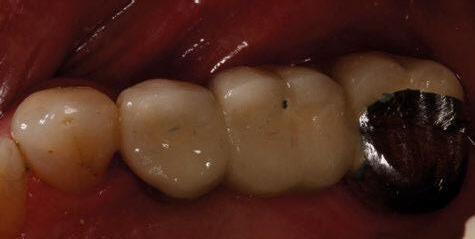

directamente a cabeza de implante para realizar una prótesis dentoalveolar de cerámica de 3 piezas, que equilibraran la oclusión y dieran soporte al labio y la mejilla (Figuras 14-17)

Durante el primer mes tras la intervención la paciente presentó epífora del ojo izquierdo que se resolvió de forma espontánea. Al año acude a consulta refiriendo dolor localizado y celulitis subcutánea originada por tejido de granulación en el brazo de la conexión más anterior.

Tras realizar curetaje quirúrgico periimplantario y tras una semana

de tratamiento antibiótico con amoxicilina y ácido clavulánico, cede la infección. Al segundo año de seguimiento, el tratamiento permanece estable y no ha presentado más complicaciones biológicas, estructurales o protésicas.